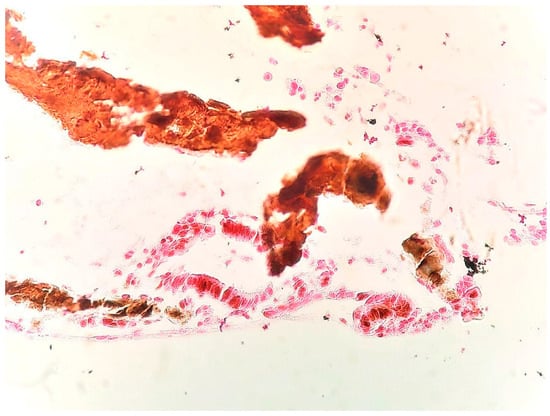

Case Report